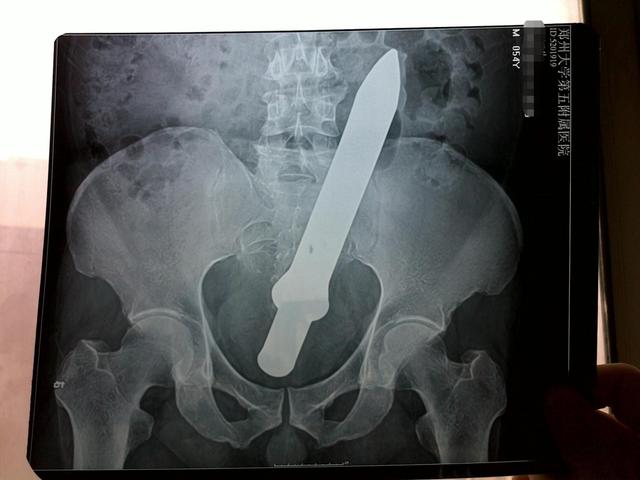

安徽一名男子因为好奇心太重,把一个长度超过30厘米的塑料棒塞进了直肠,同样是在医生的帮助下才取了出来,

郑州也有一名男子也是把一个塑料棒塞进了直肠,医生同样是大费周折,才让男子化险为夷。